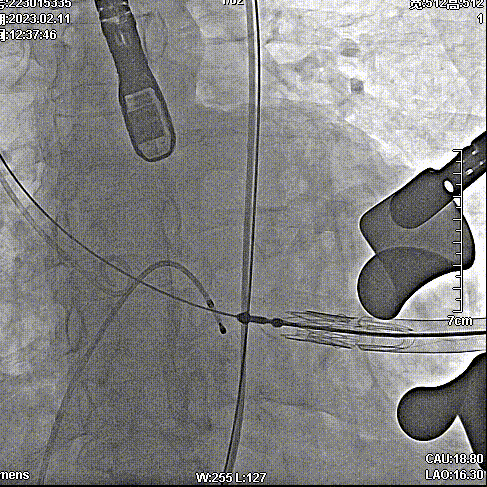

手术步骤

拔除股动脉血管鞘,缝合股动脉。手术顺利结束。